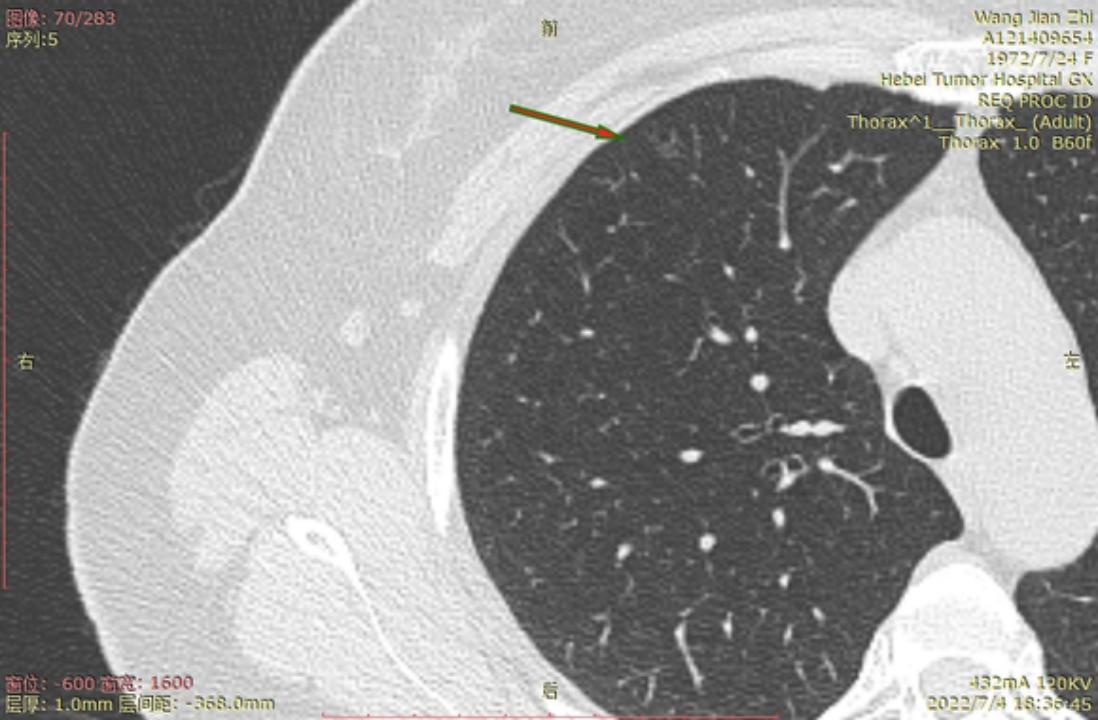

结1

结2